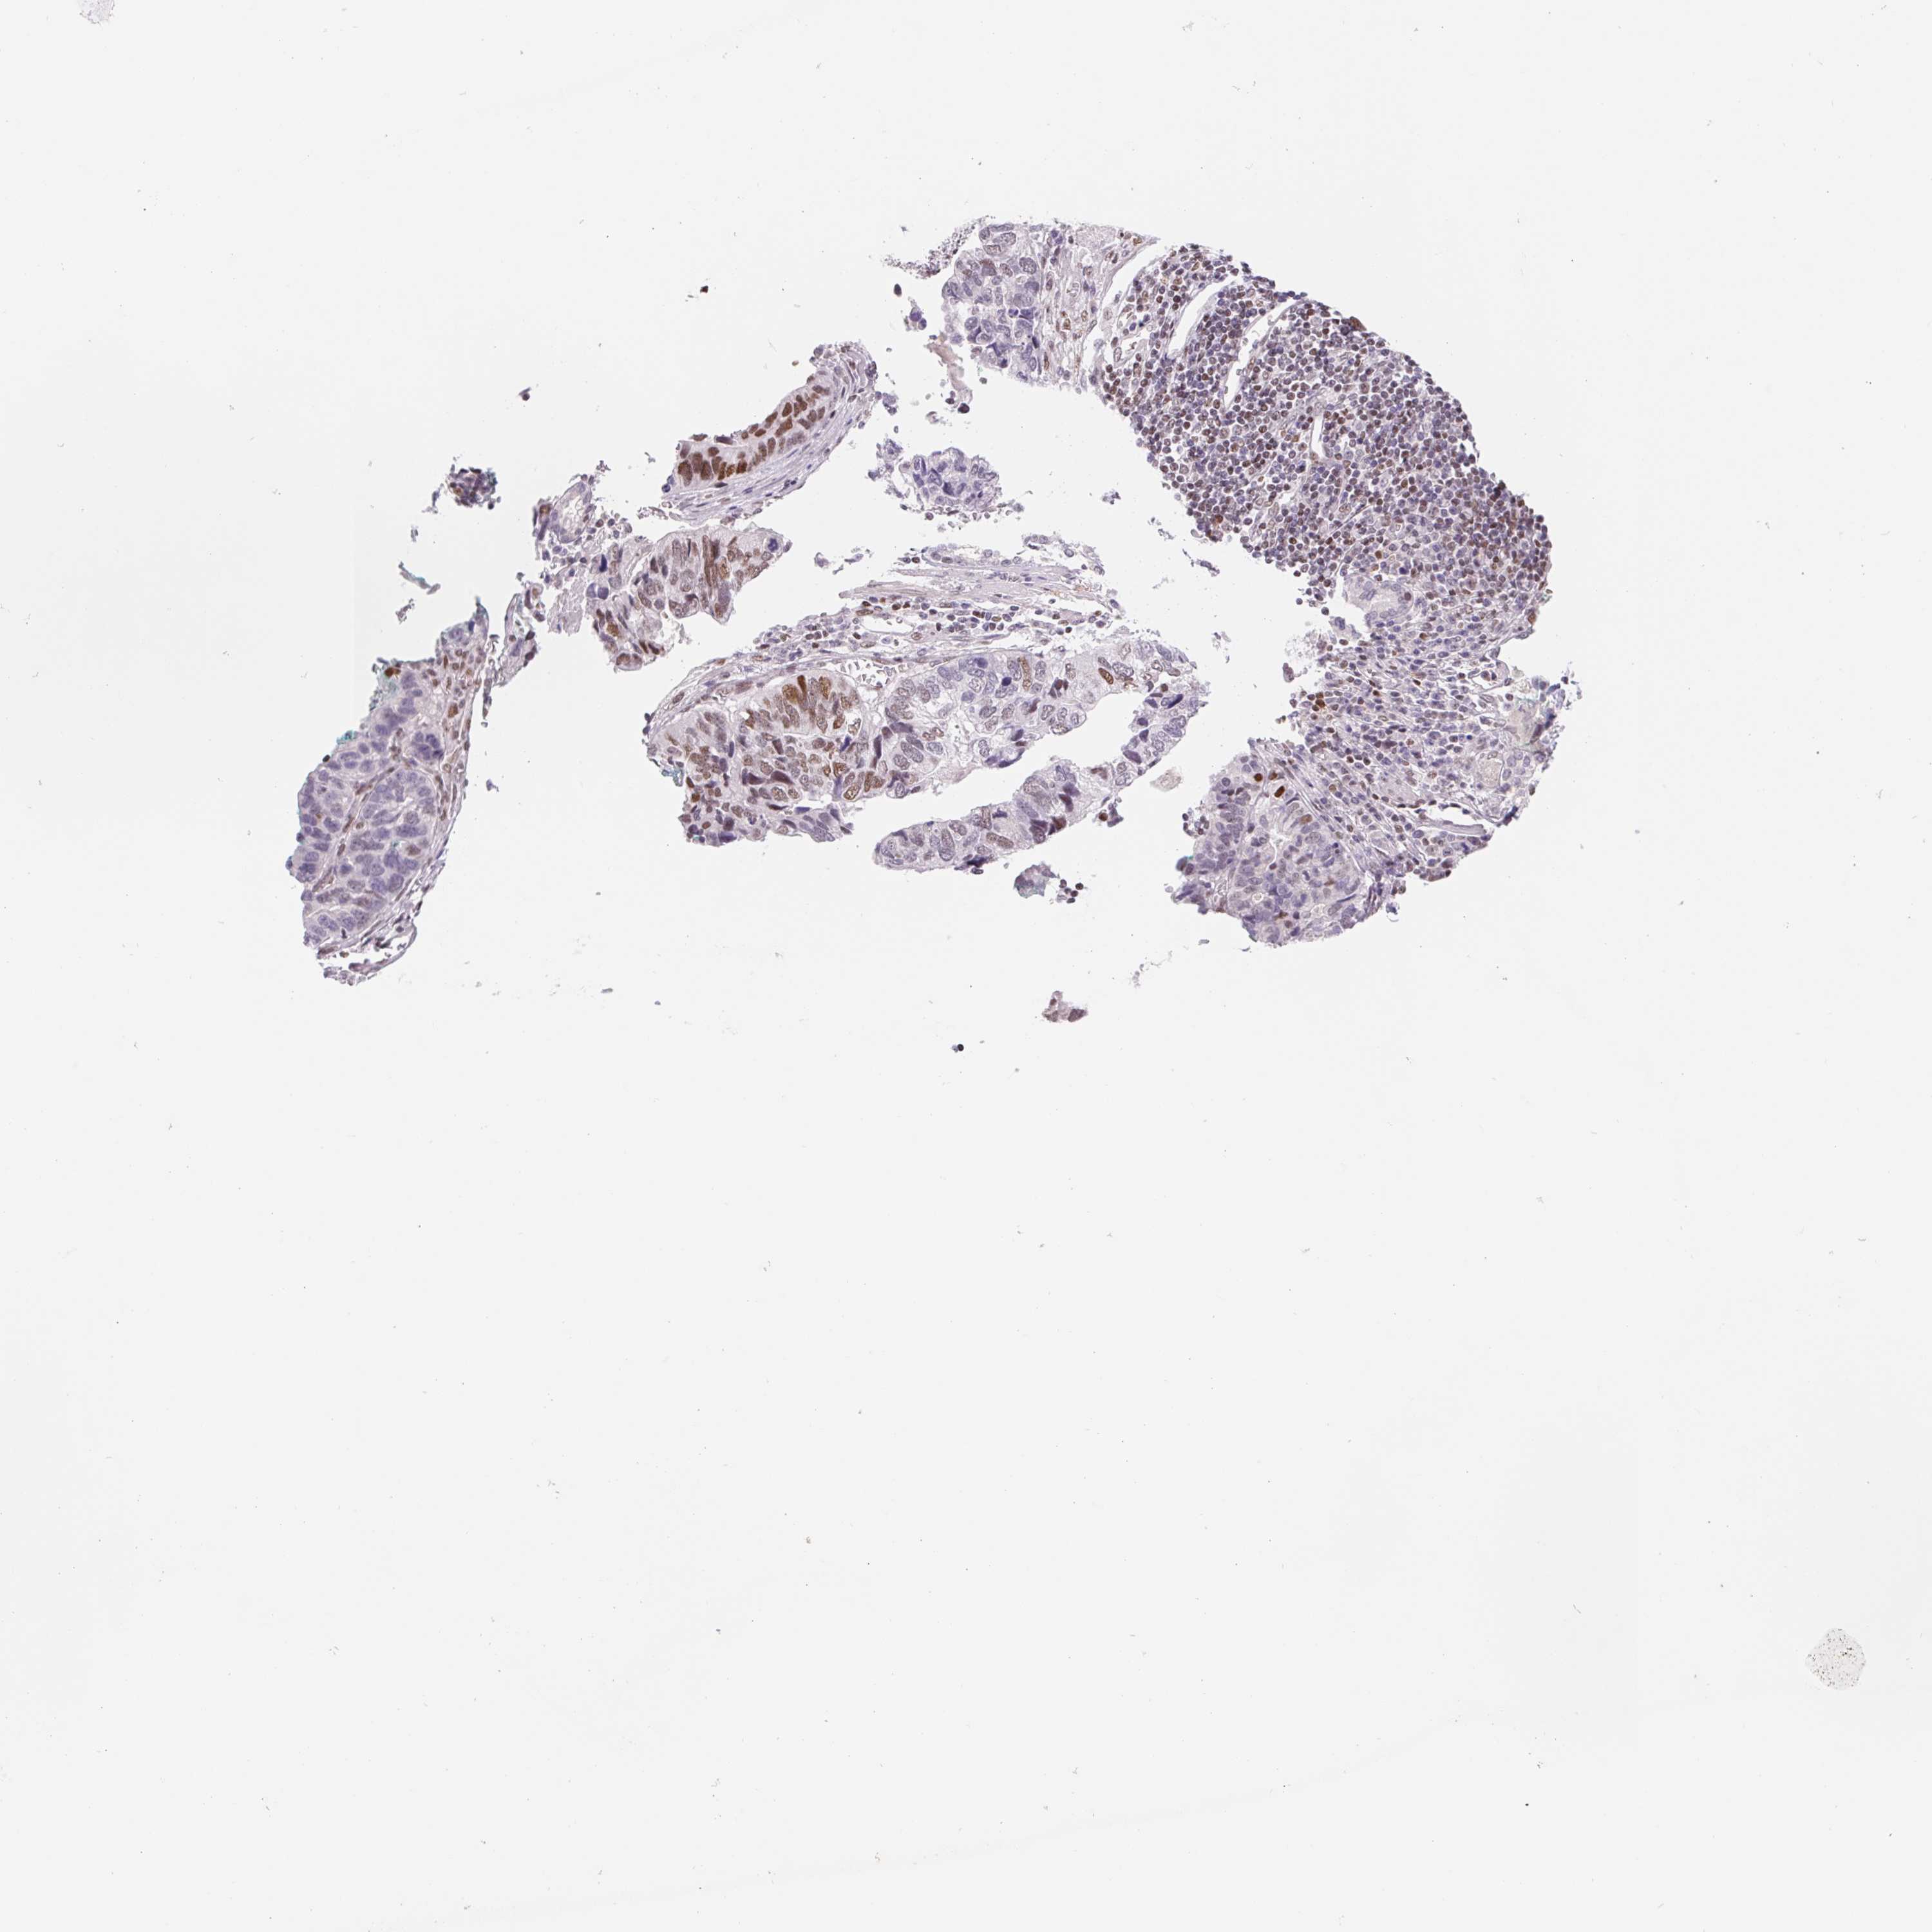

STOMACH CANCER - Protein expressioni

A mouse-over function shows sample information and annotation data. Click on an image to view it in a full screen mode. Samples can be filtered based on level of antibody staining by selecting one or several of the following categories: high, medium, low and not detected. The assay and annotation is described here.

Note that samples used for immunohistochemistry by the Human Protein Atlas do not correspond to samples in the TCGA dataset.

Antibody stainingi

Antibody staining in the annotated cell types in the current human tissue is reported as not detected, low, medium, or high, based on conventional immunohistochemistry profiling in selected tissues. This score is based on the combination of the staining intensity and fraction of stained cells.

Each image is clickable and will lead to virtual microscopy that enables deeper exploration of all samples and also displays staining intensity scores, fraction scores and subcellular localization as well as patient and tissue information for each sample.

Antibody HPA059943

Staining

High

Medium

Low

Not detected

Intensity

Strong

Moderate

Weak

Negative

Quantity

>75%

75%-25%

<25%

None

Location

Nuclear

Cytoplasmic/membranous

Cytoplasmic/membranous,nuclear

Adenocarcinoma, NOS